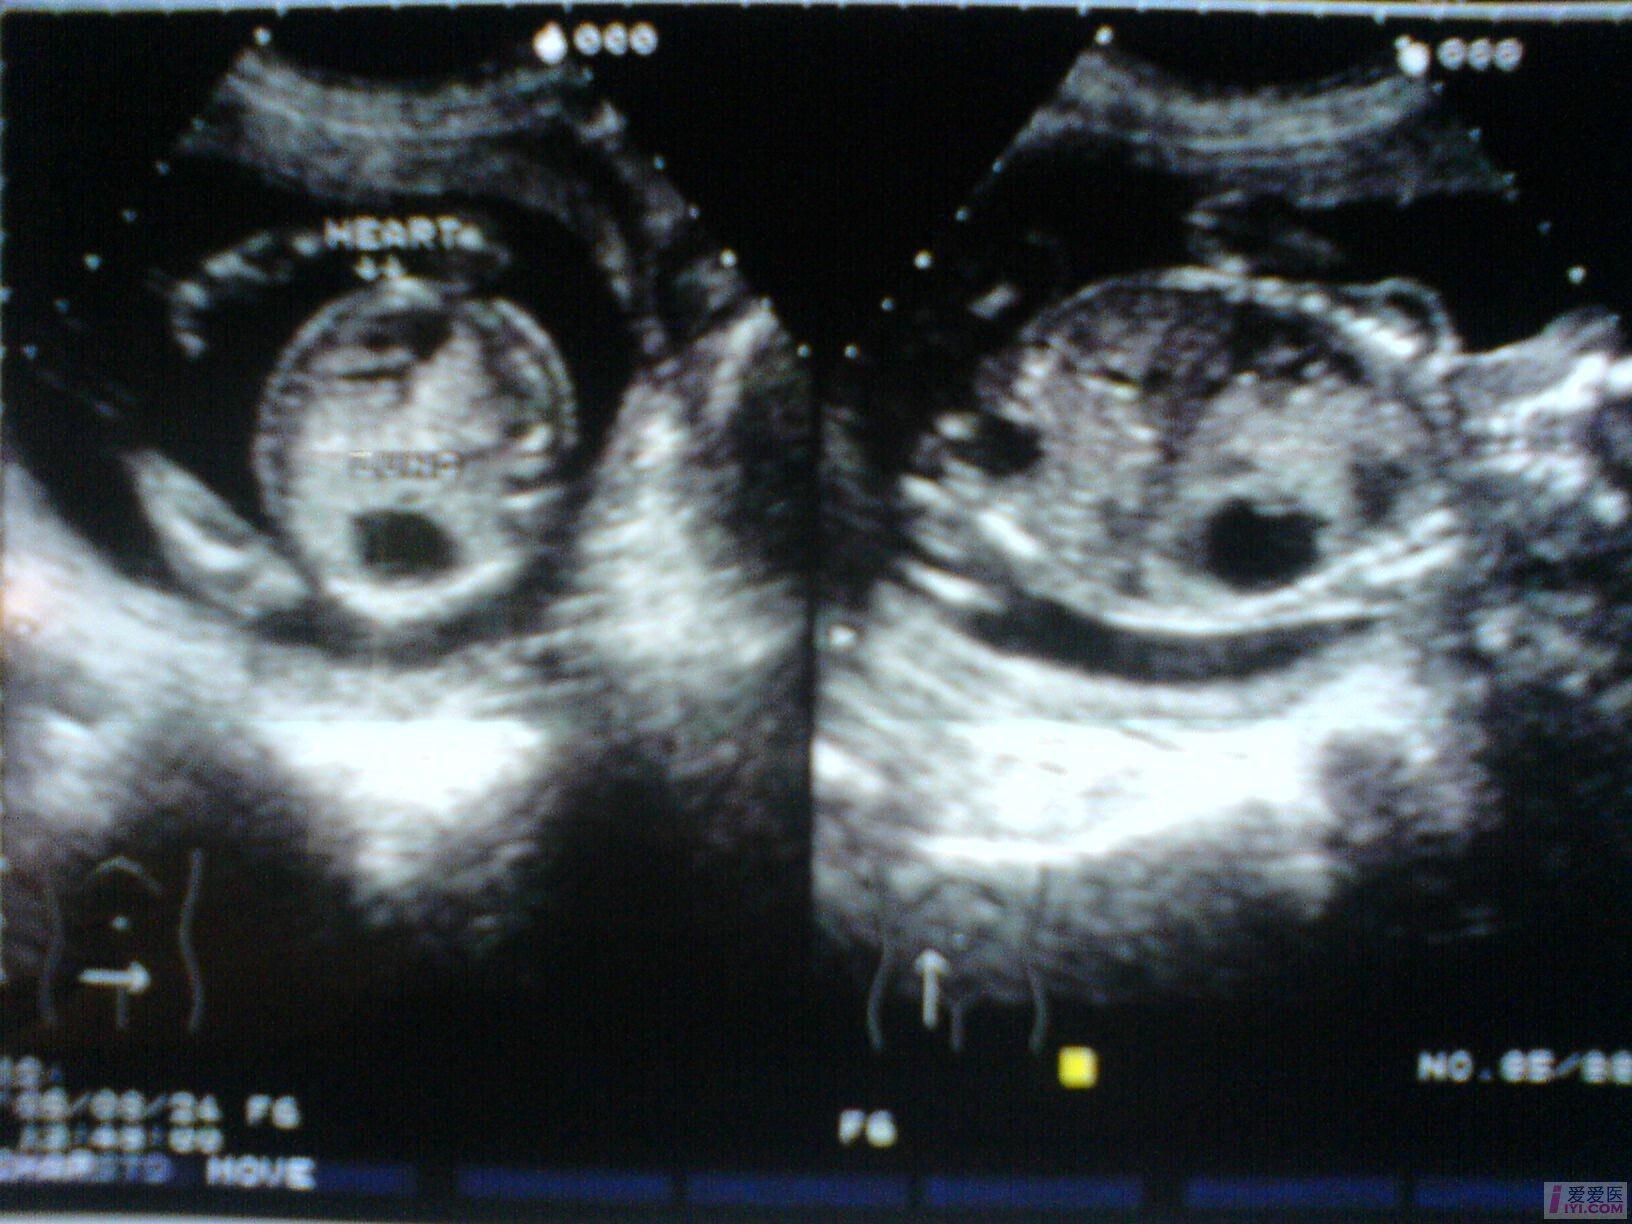

B超所见:宫内单胎妊娠,胎头双顶径51mm,股骨长35mm,胎儿脊柱完整,肺实质回声增强,右侧肺叶内见31X18X17mm不规则无回声区,边界清晰,内透声好,CDFI:无回声区内未见血流信号。胎儿心胸比例失常,心脏明显受压,胎儿肝脏增大,位置下移,占据整个腹腔,回声增粗,欠均匀,未见胃泡回声,肝脏周围见宽4mm无回声暗区。胎动活跃,胎心搏动好,胎心律150bpm,胎盘附于前壁,厚21mm,回声均匀,最大羊水暗区深度74mm,透声好。

B超提示:1.宫内中孕,单胎存活,胎儿发育符合21周。

2.胎儿肺实质回声增强,右侧肺叶囊性占位,肝大,少量腹水。

请教:该例病例可否考虑胎儿肺囊腺瘤样变? [readperm]1[readperm]